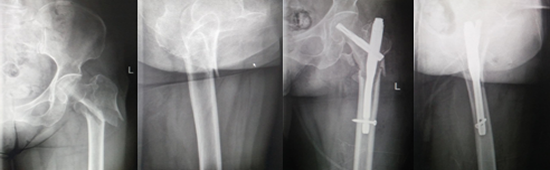

左股骨粗隆間骨折PFNA(防旋股骨近端髓內(nèi)釘)內(nèi)固定術(shù)